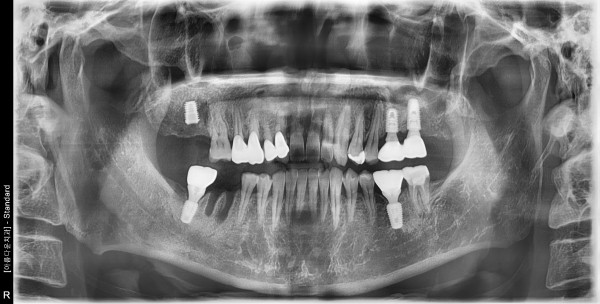

51세남자 오른쪽구치부, 하악양쪽구치부 뼈이식및임플란트식립